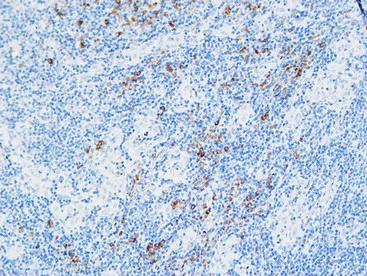

MPO Rabbit Polyclonal Antibody

Cat: APRab14056